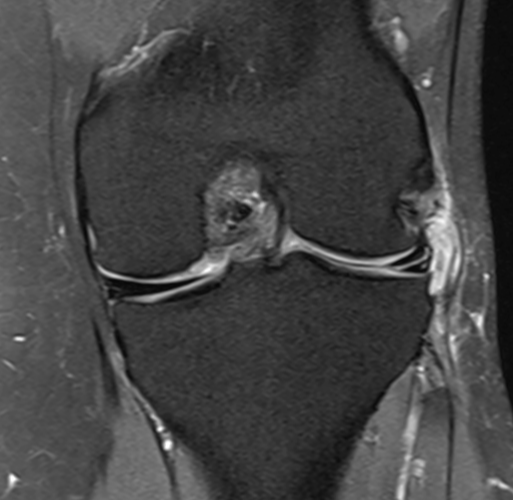

3. Medial meniscus tear + parameniscal cyst